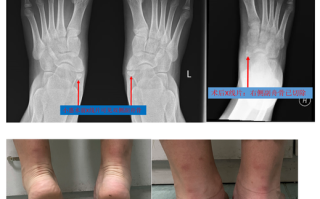

儿童副舟骨突出需要治疗吗?会影响脚部发育吗?

这是一个非常好的问题,也是很多家长在给孩子洗澡或换衣服时会发现的疑惑,儿童副舟骨突出是一种常见的先天性骨骼变异,在大多数情况下,它本身不是一种“病”,但如果它引起了症状,就需要关注和处理,下面为您详细...